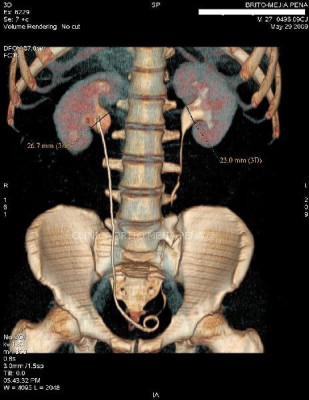

Urotac 3D